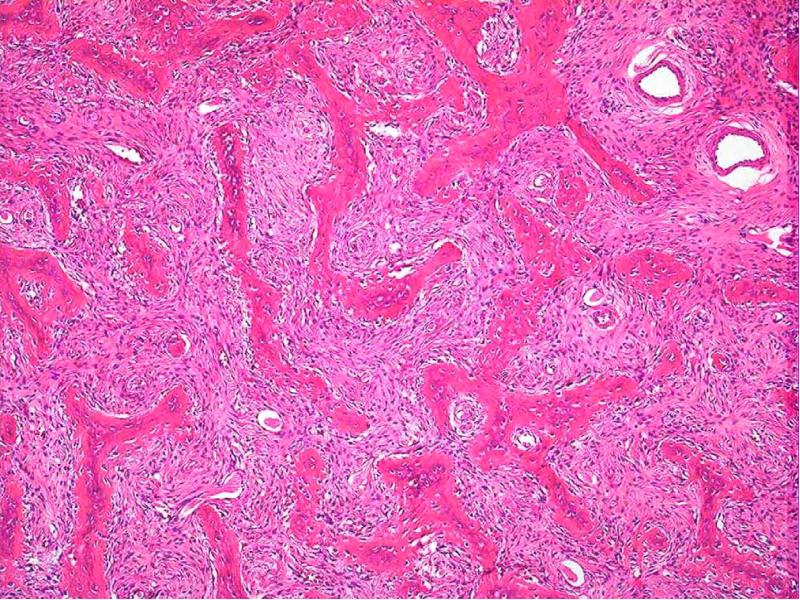

- 66. Микроскопическая картина Разрастание клеточно-волокнистой остеогенной ткани, строящей примитивные костные балочки по

- 62. Фиброзная дисплазия Опухолеподобное заболевание моно- и полиоссальное. Поражаются кости черепа, бедренные,

- 63. Макроскопическая картина Кость деформируется вследствие ее очагового увеличения («вздутия») Рентгенологически картина